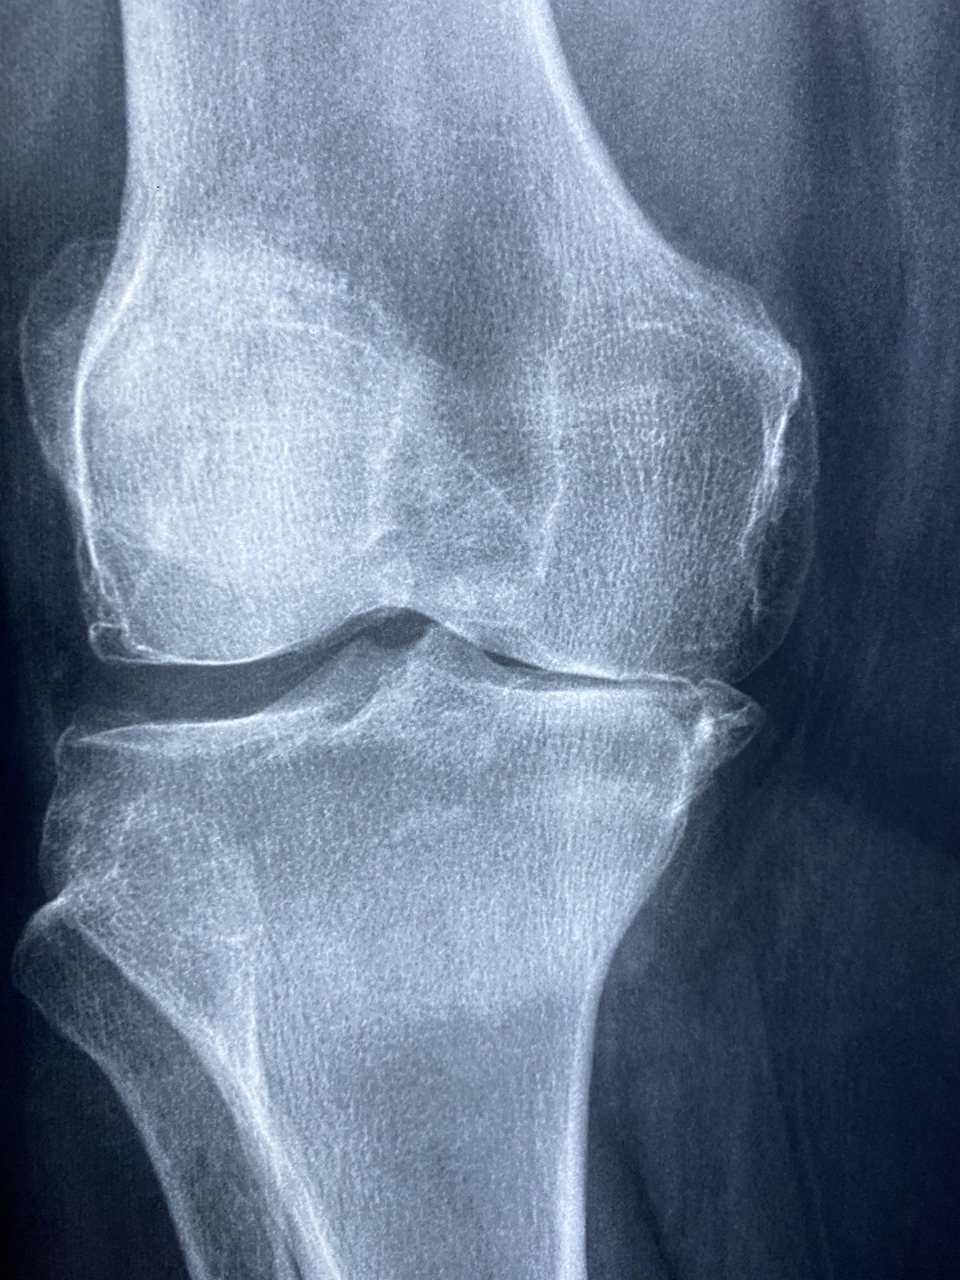

2. 관절 건강 강화

콜라겐은 연골의 주요 구성 성분으로, 관절 건강에 직접적인 영향을 미칩니다. 관절염 환자들을 대상으로 한 연구에서 콜라겐 보충제 섭취 후 관절 통증이 현저히 감소하고 관절 기능이 개선되었고 운동선수들에게 콜라겐을 보충시킨 결과, 운동 후 관절 통증이 감소하고 회복 속도가 빨라졌습니다. 이는 콜라겐이 관절 연골의 재생과 유지에 핵심적인 역할을 하기 때문입니다.